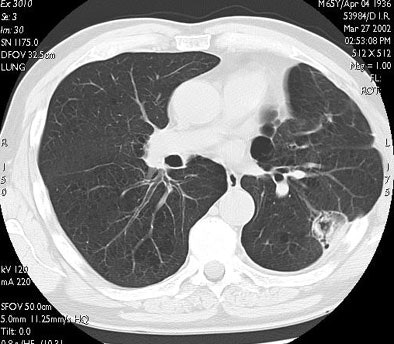

![]() |

| In the same patient, CT studies performed three months (above) and six months after treatment (below) show progressive shrinkage of the area of coagulation necrosis that exhibits central cavitation. No signs of tumor recurrence are detected. Images courtesy of Dr. Riccardo. |